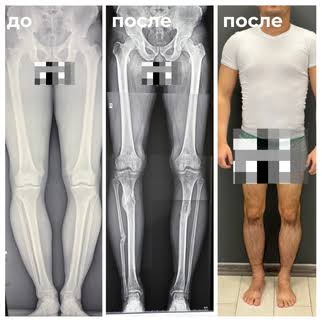

Прикиньте додсы режут себе кости, вставляют какие-то железные трубки и пластины под кожу, проводят всякие операции и жрут всякое увеличивающее размеры чтобы им тёлка всё равно не дала) казалось бы шутка из нулевых........